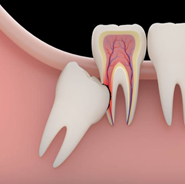

3rd Molar

In some case 3rd molar was causing discomfort, pain or damaging tooth nearby, must be extracted.

ડાહપણ દાઢ

ડાહપણ દાઢ દુ : ખાવો કરતી હોય અથવા બાજુના દાંતને નુકસાન પહોંચાડતી હોય